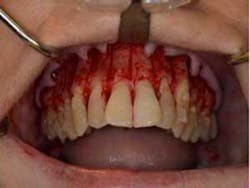

SFOT surgery was performed in the maxillary and mandibular arches with deep buccal corticotomies. Particulate, demineralized, freeze-dried bone allograft and acellular dermal matrix were used to augment the ridges.

Total treatment time: 6 months. Patient declined recommended further clear aligner refinement and fine-tuning periodontal plastic surgery.